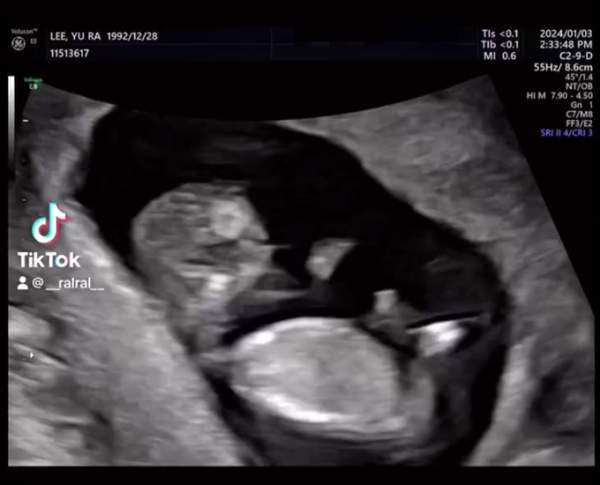

- 나이 : 1992년 12월 28일생 (2025년 기준 만 32세)

- 가족 : 1981년생 남편 (11살 연상, 비연예인), 딸 1명 (2024년 7월 12일 출생)

2024년에 랄랄은 유튜브를 통해 결혼과 임신 사실을 공개하며 많은 관심을 받았다. 남편은 1981년생의 비연예인으로, 나이는 랄랄보다 11살 많다. 부부 사이에는 딸 한 명이 있는데 2024년 7월 12일에 출산했다. 방송에서는 딸을 소개하며 “할머니랑 사는 느낌”이라며 웃음을 자아내는 발언을 하기도 했다.